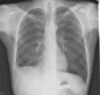

Figure 1

Initial chest radiograph. Increasing areas of confluent airspace disease involving the right middle and lower lobes and stable patchy airspace opacities involving both lungs with stable reactive lymphadenopathy